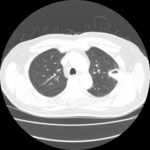

Signo de "halo" en la aspergilosis pulmonar temprana

De la colección del Dr. P. Chandrasekar; utilizada con autorización

Ver esta imagen en el contexto de la/s siguiente/s sección/es: